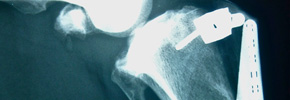

Kreuzbandriss beim Hund

Anders als beim Menschen reißt das vordere Kreuzband beim Hund meistens ohne ein Trauma._Degenerative Veränderungen und chronische Überlastung sind beim Hund die häufigsten Ursachen. Ein gerissenes Kreuzband muss beim Hund operativ versorgt werden (Extrakapsulärer Bandersatz oder TTA).